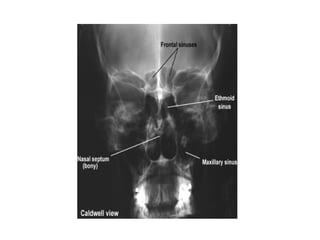

• X-ray – Caldwell’s view (Occipito-frontal view)

• CT Scan

• X-ray –Caldwell’s view (Occipito-frontal view)